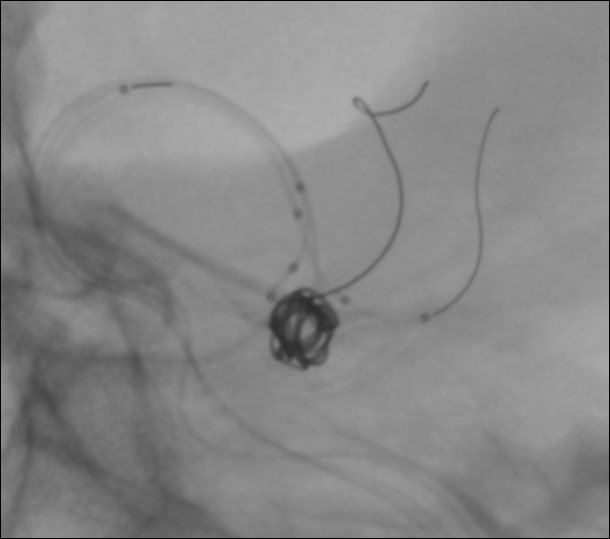

En este aneurisma se realizó la cateterización con dos balones de remodeling Eclipse 2L con microguías Traxcess y Ashahi .014, realizando dos cambios de curva para el cateterismo distal. El acceso proximal se realizó con un introductor largo Ballast .088 de 90cm que permite el uso de dos balones y un microcatéter para introducir los coils.

Con un buen posicionamiento de los balones se logró el cierre completo del aneurisma con seguridad y control garantizando la permeabilidad de las ramas. En este caso no se completó el tratamiento con stent por que la paciente debe someterse a una cirugía reciente.